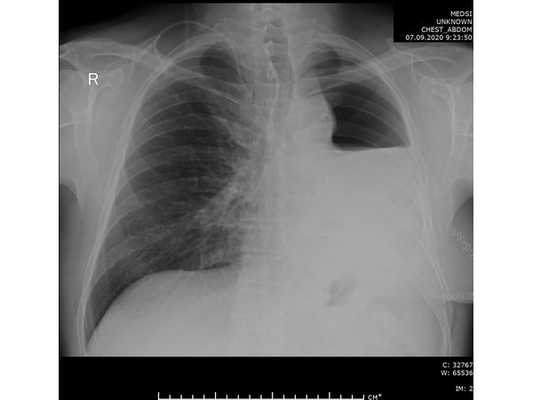

Рентгенография органов грудной клетки

Ранняя диагностика рака легких может быть проведена и при помощи рентгенографии органа. В таком случае для наибольшей эффективности снимки делаются сбоку и со стороны спины.

При наличии онкологии на снимках будут замечены участки, вызывающие сомнения.